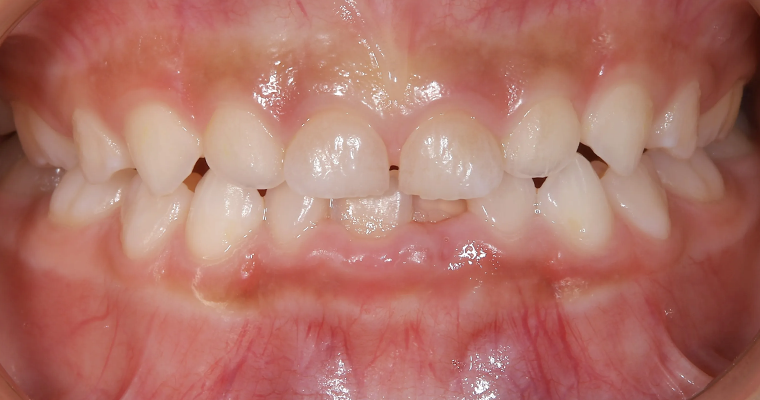

CASE.3 歯並びが悪い

正面観

BEFORE

AFTER

| 主訴 | 歯並びが悪い 乳歯と永久歯が重なっている 歯がまっすぐはえてこない |

|---|---|

| 治療期間 | 6-7ヶ月 |

| 治療費 | 440,000円(税込) ※調整、器具、治療後にお渡しするEFLine(矯正後の後戻りを防ぐ器具)も全て込みでの金額となっております。 |

| 治療内容 | 拡大床矯正 EF Lineで筋機能療法 |